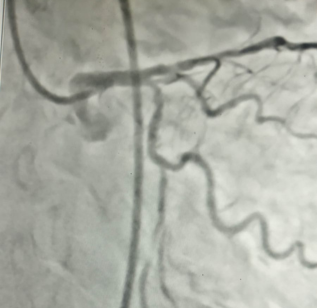

2 Stentless Angioplasty/ Metal less PCI( Percutaneous Coronary Intervention)

We have done 2 Stentless Angioplasty/ Metal less PCI( Percutaneous Coronary Intervention) in our centre ( 1 st time in this district )with Drug Eluting balloon in the last few days.

Drug-eluting balloons (DEBs) are primarily used to treat restenosis, especially in-stent restenosis (ISR) and de novo lesions, particularly in smaller vessels and situations where avoiding a stent is preferred. DEBs offer a way to deliver medication locally to the vessel wall to prevent re-narrowing after angioplasty. Specific Indications for DEBs: In-stent restenosis (ISR): DEBs are particularly useful in treating restenosis that occurs within previously implanted stents, especially bare-metal stents (BMS). De novo lesions: DEBs can be used to treat new blockages in coronary arteries, especially in situations where stent implantation is not ideal, like in small vessels or bifurcation lesions. Small vessel disease: DEBs are a good option when dealing with smaller coronary arteries where stent placement might be challenging or less optimal. Bifurcation lesions: In cases where a blockage occurs at a branch point of a coronary artery, DEBs can be used to avoid stenting both branches. Acute myocardial infarction (AMI): DEBs can be used in the setting of acute heart attacks, particularly when a stent is not immediately necessary. Femoropopliteal occlusive disease: DEBs are also used in the peripheral arteries, such as the femoropopliteal arteries, to treat blockages in the legs. High bleeding risk patients: DEBs may be preferred over DES in patients who cannot tolerate long-term dual antiplatelet therapy, according to some studies.